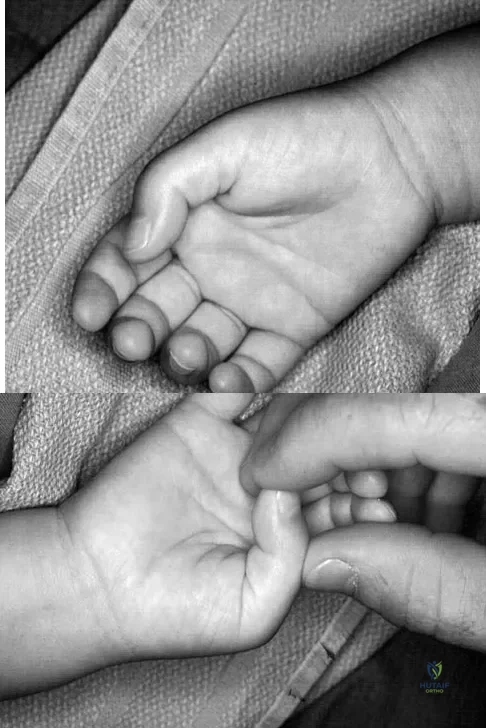

A 6-year-old child has a fixed flexion deformity of the interphalangeal (IP) joint of the right thumb. The thumb is morphologically normal, with a nontender palpable nodule at the base of the metacarpophalangeal joint. Clinical photographs are shown in Figures 42a and 42b. Based on these findings, what is the treatment of choice?

Explanation